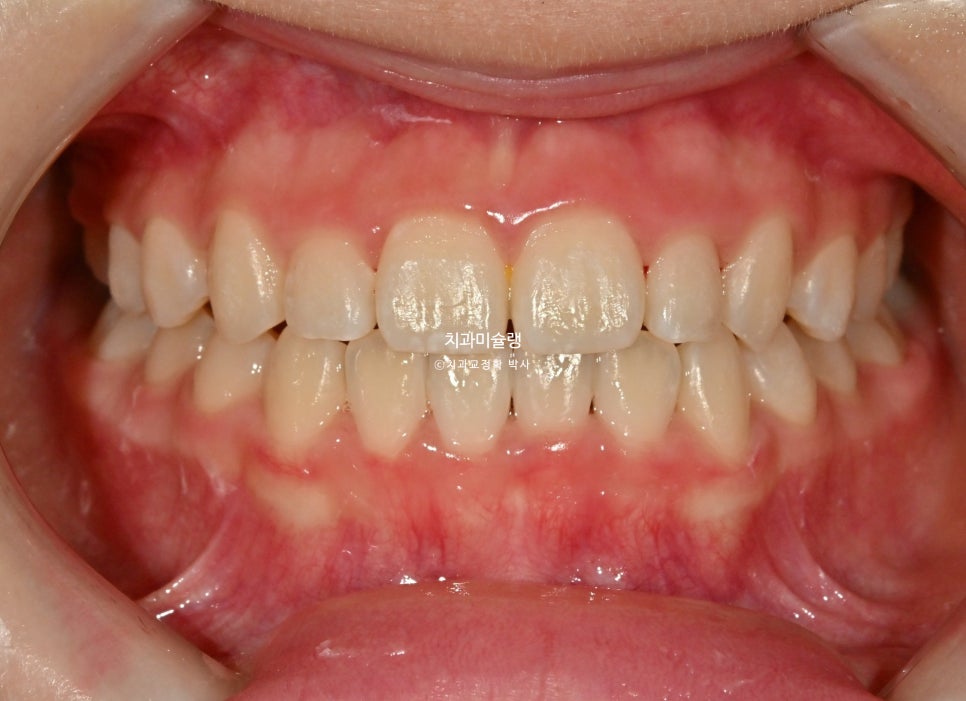

2026년 2월 – 치료 완료

2026년 2월, 정상교합이 달성되어 치료를 마무리 합니다.

중심선은 잘 맞으며 절단교합으로 인항 개방교합은 해소되었습니다.

어금니 교합관계는 1급을 달성.

3급 교합관계를 1급으로 만들기 위해 치료기간 내내 3급 고무줄을 사용했습니다.

결과가 성인교정치료 결과에 준한만큼 유지장치도 성인과 동일하게 들어갑니다.